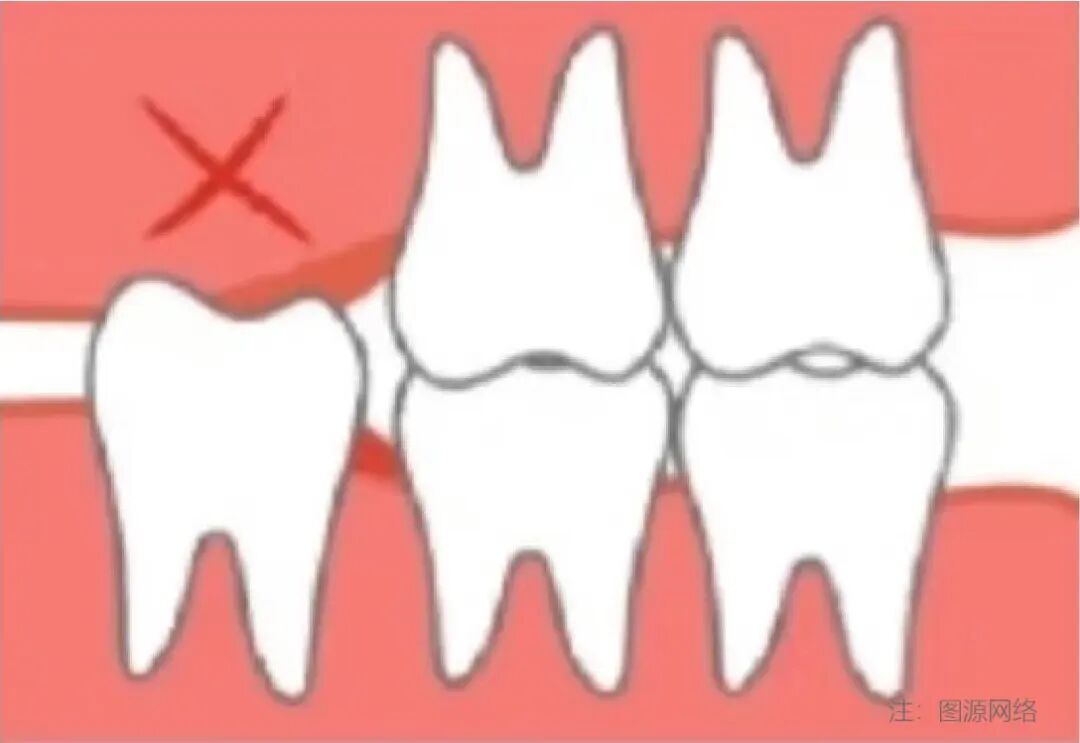

4)侵犯邻牙:邻牙不易清洁,容易龋坏/压迫牙根,引起牙根吸收